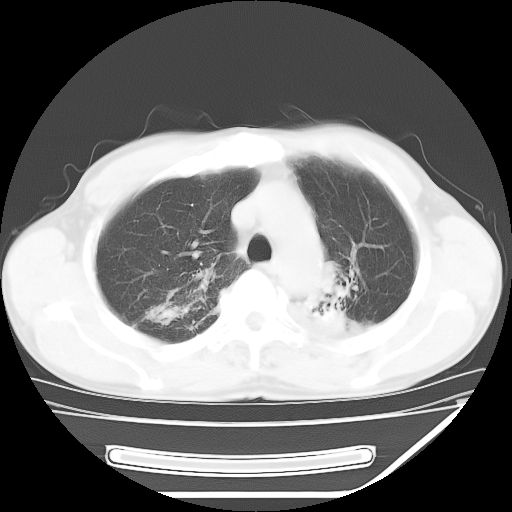

男,59岁,“结核性胸膜炎”30余年,胸部经常疼痛,多次x检查提示“肺部”炎症。腹部疼痛5日,b超提示:“肝内短管结石,余显示不清,建议进一步检查。”

两肺结核并右侧胸腔积液;脾脏、腹腔及腹膜后淋巴结结核[陈旧性];肝内胆管结石

胸部腹部都是结核(双肺。纵隔淋巴结,肝脏,脾脏,肠系膜)

两肺结核并右侧胸腔积液;脾脏、腹腔及腹膜后淋巴结结核[陈旧性];肝内胆管结石。直肠息肉?